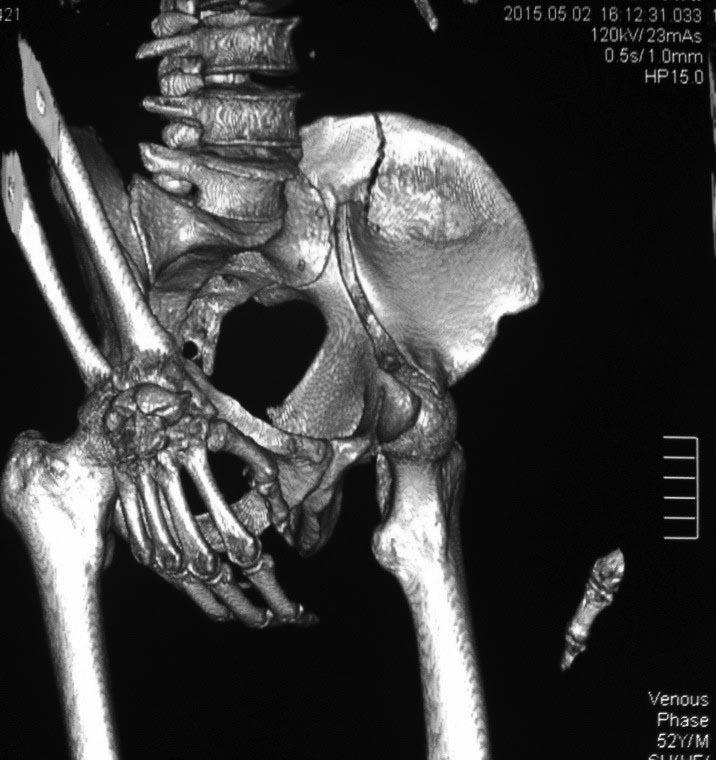

Это высокий перелом передней колонны вертлужной впадины (62A3.2).

Появились новые проекции. Да, это высокий перелом передней колонны левой вертлужной впадины со смещением.

Да, я понимаю, что предпочтительнее всего накостный синтез. Но если сравнивать АВФ с миниинвазивным, то ни тот ни другой не гарантируют 100%й репозиции. Перелом начинается с передней стенки впадины, идет вверх до крыла, а сзади спускаясь, останавливается едва достигнув задней колонны. Да, задняя колонна цела. Есть поперечные срезы КТ (сейчас показать не могу), где это четко видно. Перелом не завершенный. Учитывая этот факт, я и подумал о возможности АВФ. Простите мне мою упрямость)).

Относительно диагноза соглашусь с коллегами повреждение крыла и передней колоны вертлужной впадины ближе к типу В по классификации Летурнеля, хотя не в полной мере ей соответствует. Согласно Матта смещение более 3х мм -показание к открытому остеосинтезу, в данном случае скорее из илиоингвинального доступа или Стоппа. Хотелось бы конечно увидеть остальные срезы и рентгенограммы.

В последнее время, из-за красоты участился показ 3D снимков, хотя надо начать c обычных, и, по необходимости, компьютерная томография с 3D! Без головки бедра 3D покажет общую картину и вовлечение сустава, а более детально только в срезах КТ.

Данная картина показывает очень редкий перелом передней колонны, но перед операцией еще раз надо просмотреть обещанные дополнительные КТ срезы.